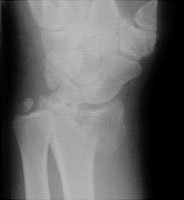

Reverse Barton Fracture

The reverse Barton fracture refers to an intraarticular fracture through the distal radius. Although it is similar in appearance to a Smith fracture, the Smith fracture is not intraarticular. The reverse Barton fracture involves the volar rim of the radius while the conventional Barton fracture involves the dorsal rim. The fracture is caused by direct trauma.

- Click on the image for a larger versionALateral radiograph of the wrist. This shows a displaced fracture of the volar rim of the radius.

- Click on the image for a larger versionBOblique radiograph of the wrist. The intraarticular nature of this fracture can be appreciated.